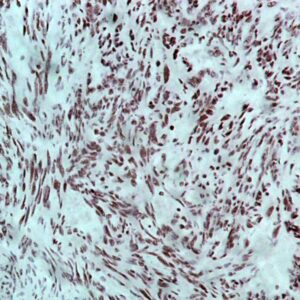

BioGenex has pioneered the development of miRNA research and diagnostics tools with leading-edge products. Currently, we offer over 240 ready-to-use (RTU) Super Sensitive™ Nucleic Acid (SSNA) miRNA ISH probes for accurate and early tumor diagnosis. These probes are sensitive enough to detect low-abundant miRNA(s) that are often required to identify biomarkers. They have a high melting temperature enabling stringent washes to remove non-specific binding. BioGenex miRNA probes are dual-end labeled with an anti-fluorophore to amplify the signal and yield clean and intense staining.